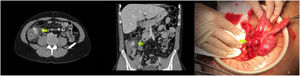

A 33-year-old man consulted for abdominal pain of 2 days’ evolution radiating to the right iliac fossa with fever of 38.3 °C. Laboratory tests showed leukocytosis of 13,480 cells/mL and C-reactive protein of 56 mg/l. An abdominal CT scan was performed, showing a thickened tubular structure with calcifications in its interior depending on the cecum, with inflammatory changes suggestive of acute appendicitis (Fig. 1).

A laparotomy was performed where a normal calibre appendix was visualised and the presence of a perforated cecal diverticulum with enterolithiasis inside it, adjacent to the ileocaecal valve was observed (Fig. 1), so an ileocecectomy with mechanical lateral anastomosis was performed.